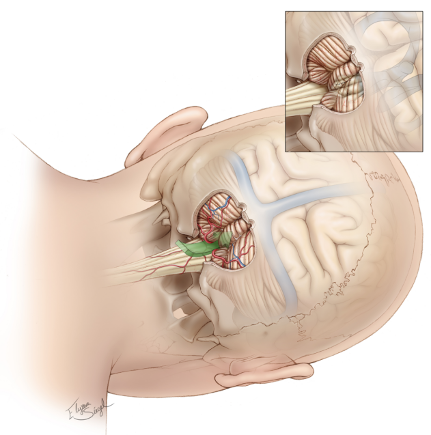

Surgical strategy: tumor resection via suboccipital midline approach, right lateral position

The ability to completely excise the tumor remains the primary determinant of ependymoma (regardless of supratentorial/infratentorial, molecular typing). For supratentorial ependymoma growing toward the lateral foramen of the quadrigeminal ventricle, the focus needs to be on protecting the lower group of cranial nerves, delineating the lateral interface of the medulla oblongata, combining blunt and sharp dissection, and making full use of the arachnoid interface.